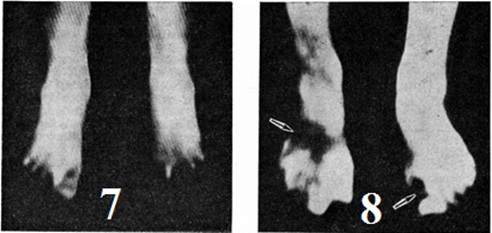

Зона демаркационного воспаления возникает по краю некроза в виде более или менее широкой красной полосы, отчётливо выраженной на 10—12-й день. При микроскопическом исследовании выявляется гнойное воспаление. На 3-й недель оно сменяется пролиферативными процессами, проявляющимися разрастанием грануляционной ткани. Если демаркация развивается на уровне сустава, в полости последнего скапливается гной. При этом суставной хрящ частично разрушается. Зона восходящих дистрофических и очаговых некротических изменений формируется проксимальнее зоны демаркационного воспаления. Она не имеет чётких границ из-за отсутствия видимых невооруженным глазом изменений кожных покровов. Дистрофические, некротические и вторичные воспалительные процессы обнаруживаются здесь только при микроскопическом исследовании. Если после Отморожение длительно сохраняются расстройства микроциркуляции или возникают нарушения кровообращения воспалительного характера, дистрофические и некротические процессы могут нарастать, распространяясь проксимальнее зоны демаркационного воспаления. В костной ткани выше границы демаркации происходят процессы перестройки в виде остеокластической резорбции (рисунок 4) и новообразования костных перекладин пролиферирующими остеобластами. В дальнейшем в артериях и венах обнаруживается склероз стенок, разрастание внутренней оболочки и организация тромбов, что приводит к сужению просвета сосудов (рисунок 5). Развиваются невриты (смотри полный свод знаний), которые морфологически проявляются разрастанием аксонов в виде невром, пролиферацией эндоневрия и периневрия. Клиническая картина. Основными симптомами Отморожение в дореактивном периоде являются побеление кожи в зоне охлаждения (цветной рисунок 7) и потеря чувствительности в охлаждённых тканях. При Отморожение, возникшем во влажной среде (промокшая обувь), нередко отмечаются синюшность и покраснение кожи поражённых конечностей (а именно они чаще всего поражаются), усиливающиеся после согревания. Пострадавшие жалуются на тяжесть в конечностях, потерю чувства опоры, невозможность самостоятельно ходить. Общее состояние больных при Отморожение конечностей может сохраняться неизменённым, однако в случаях, когда Отморожение сопровождается значительным общим охлаждением тела, могут наблюдаться признаки охлаждения организма (смотри полный свод знаний) — состояние депрессии, нарушение дыхания, одышка, тахикардия. При тяжёлых Отморожение возможно падение АД и развитие шока (смотри полный свод знаний). Клиническая картина Отморожение в реактивном периоде проявляется серозным или серозно-геморрагическим воспалением (холодовый дерматит) с исходом в асептический некроз. Наиболее ранними признаками реактивного периода являются развитие отёка, покраснение (с синюшным оттенком) кожи (цветной рисунок 8), затем (кроме отморожения I степени) появление пузырей. Геморрагическое содержимое пузырей чаще всего свидетельствует о том, что тяжесть Отморожение превышает вторую степень. Уже в первые минуты согревания, ещё до развития видимых воспалительных и деструктивных изменений, возникает боль, интенсивность и длительность которой зависит от тяжести поражения. Определить глубину и тяжесть поражения, то есть степень Отморожение, его распространение по площади в первые часы и даже дни после согревания не представляется возможным. О масштабах деструктивных изменений в этот период можно судить лишь предположительно, более явно признаки некроза появляются лишь в конце первой декады. Отморожение I степени возникает после относительно короткой экспозиции холода, при которой не развивается значительного понижения температуры тканей. При этой степени Отморожение общее состояние больного нарушается незначительно. Сразу после прекращения экспозиции холода и согревания больные жалуются на жгучие боли в области поражения холодом, ощущение зуда, чувство колотья, развиваются гиперестезии (смотри полный свод знаний: Чувствительность) и парестезии (смотри полный свод знаний). Эти ощущения сохраняются несколько дней. Поражённая кожа краснеет, припухает, отёчность часто носит характер пастозности (цветной рисунок 8). Отёк в ряде случаев распространяется не только на ткани, подвергавшиеся непосредственному охлаждению, но и прилегающие к ним. Особенно выраженный отёк наблюдается на лице, ушах, крайней плоти. Пузыри не появляются. Отёк и пастозность ткани обычно уменьшаются через 5—8 дней, процесс заканчивается обширным шелушением поверхностных слоёв эпидермиса. Выздоровление наступает через 7—10 дней. В последующем пострадавшие отмечают повышенную зябкость в зоне поражения, часто остаётся пигментация кожи. Отморожение II степени вызывает значительные болевые ощущения, неприятное чувство напряжения тканей. Пузыри (цветной рисунок 3) появляются в течение 2—3 суток после поражения, иногда позже — на протяжении первой недели реактивного периода. Локализация пузырей в области поражения, их число, размеры могут быть различными. Они редко образуются на ладонной и подошвенной поверхности, а если возникают в этих зонах, то обычно имеют меньшие размеры, чем на тыле стопы или кисти. Содержимое пузырей в зависимости от концентрации фибрина может быть жидким или желеобразным. На дне пузыря скапливается фибрин в виде налёта, равномерно покрывающего неповреждённый базальный (ростковый) слой эпидермиса по всей поверхности отслойки повреждённых его пластов. Окраска содержимого пузырей желтоватая. Отёк при отморожении II степени значительный, захватывает обширные зоны, в том числе и не подвергавшиеся непосредственному охлаждению. Поверхность пузырей весьма хрупкая и во многих случаях разрушается самопроизвольно или при неосторожных движениях больного. Заживление, не осложнившееся нагноением, протекает 2—3 недель, рубцов не остаётся. В последующем, как и после отморожения I степени, сохраняется повышенная чувствительность пострадавшей кожи к холоду. Отморожение III степени сопровождается сильными болями, которые в ряде случаев носят иррадиирующий характер. Потеря чувствительности в области поражения продолжается и в раннем реактивном периоде, чаще всего она наблюдается в зонах, в последующем подвергающихся омертвению. Кожа поражённого участка остаётся холодной, принимает синюшную окраску, образовавшиеся пузыри наполнены геморрагическим содержимым (цветной таблица, ст. 80, рисунок 4). Пульс на стопе (или запястье) ослабевает либо вовсе исчезает, что связано с нарастающим напряжением тканей вследствие сильного отёка. В конце первой недели отёк начинает постепенно спадать, и появляются чётко отграниченные области потемневших некротизирующихся тканей. При присоединении гнойной инфекции отёк продолжает нарастать. Демаркационные репаративные процессы значительно замедляются. При развитии сухой гангрены образуется струп, который отторгается через 2—3 недель, и под ним обнаруживается поверхность, покрытая грануляционной тканью. Период рассасывания и отторжения некротизированных тканей, эпителизация гранулирующей поверхности протекают в течение нескольких недель с образованием глубокого рубца. В редких случаях наблюдается частичное или полное отторжение органа (носа, ушных раковин, полового члена). Отморожению IV степени чаще всего подвергаются конечности. Зона омертвения при этом не всегда ограничивается пальцами рук или ног, но распространяется на кисть, стопу, редко на дистальные части голени или предплечья. В самом начале реактивного периода отёк развивается на площади, значительно превышающей область непосредственного охлаждения. Некроз может протекать по типу влажной гангрены либо в виде мумификации тканей. Последняя форма омертвения развивается преимущественно при поражении пальцев (цветной рисунок 5). Течение процессов отторжения омертвевших тканей, развития грануляций, эпителизации и рубцевания весьма длительное. Так, демаркация зоны омертвения при поражении пальцев наступает через 2— 4 недель, а при некрозе, распространившемся на диафизы костей, в некоторых случаях заканчивается лишь спустя 2—3 месяцев Умеренное длительное охлаждение нижних конечностей при невозможности просушить обувь грозит Отморожение стоп с особой клинической картиной. Наблюдалось массовое возникновение таких Отморожение у военнослужащих, сплавщиков, рыбаков и др. (смотри полный свод знаний: Траншейная стопа). При непостоянном, но систематически повторяющемся охлаждении возникает, главным образом на пальцах рук, своеобразный дерматит (смотри полный свод знаний: Ознобление). Пребывание в холодной воде также может вызвать Отморожение Однако, поскольку в водной среде человек теряет во много раз больше тепла, чем при такой же температуре в воздухе, доминирующее значение приобретает опасное для жизни общее охлаждение организма, а местные поражения не всегда успевают развиться. Но если они возникают, то текут тяжело. Уже во время экспозиции холода появляются боли в конечностях, нередко судороги; в последующем возникают парестезии, потеря чувствительности; быстро развивается отёк конечности; пульс на периферии исчезает. При длительном пребывании человека в воде может произойти мацерация кожи, в поражённых конечностях обнаруживают циркуляторные и невротические нарушения, образуются пузыри, в тяжёлых случаях некротизируются дистальные части конечностей. Процесс восстановления происходит медленно, иногда с развитием ангиотрофоневроза (смотри полный свод знаний). Осложнения. Тяжесть течения Отморожение и их исход во многом определяют местные и общие осложнения. Наиболее часто отмечаются инфекционные осложнения. При отморожении II степени инфицирование содержимого пузырей может привести к гибели базального слоя эпидермиса и придатков кожи, что значительно удлиняет период заживления, ведёт к образованию рубцов. После отморожений III и IV степени возможно развитие всех разновидностей раневой инфекции: анаэробной, гнилостной, гнойной (смотри полный свод знаний: Анаэробная, инфекция, Гнилостная инфекция, Гнойная инфекция). При отморожении III степени такие осложнения наблюдаются у 10—15%, при отморожении IV степени — у 17— 20% больных. Гнойная инфекция отличается исключительным разнообразием. По данным Т. Я. Арьева, подкожные и межмышечные флегмоны за пределами демаркационного воспаления составляют около 25% всех местных гнойных осложнений, нередко возникает рожа; эти осложнения могут сопровождаться гнойными флебитами и тромбофлебитами, лимфангиитами и лимфаденитами. Из нагноившихся лимфатических, узлов формируются абсцессы и аденофлегмоны. При прохождении демаркационной линии через кость воспаление может приобрести характер прогрессирующего остеомиелита (смотри полный свод знаний), при прохождении через сустав — прогрессирующего гнойного остеоартрита (смотри полный свод знаний). Распространённые местные нагноительные процессы сопровождаются гнойно-резорбтивной лихорадкой (смотри полный свод знаний), которая при длительном нагноении приводит к раневому истощению (смотри полный свод знаний: Травматическое истощение). Наблюдаются также изменения нервов, кровеносных и лимфатических, сосудов. Возможна клинические, картина ишемии конечности. У больных с холодовым нейроваскулитом резко ослабевает пульсация сосудов в дистальных частях конечностей, отекают руки и ноги, сохраняется усиленное потоотделение, вследствие чего конечности становятся влажными. Больные ощущают чувство распирания, сдавления, жжения в поражённых конечностях. Изменяется тактильная чувствительность в области кистей и стоп, больные не могут выполнять точных движений, уверенно захватывать предметы, инструменты, теряют чувство опоры при ходьбе. В некоторых случаях после Отморожение развивается повышенная тактильная чувствительность, при этом прикосновение, сдавление, нагрузка на конечности, ношение обуви сопровождаются болевыми ощущениями. Н. И. Батыгина, К. Я. Журавлева считают, что перенесённое Отморожение ног, осложнённое Холодовым нейроваскулитом, часто является причиной облитерирующего эндартериита. На фоне нервно-сосудистых расстройств у больных развиваются дерматозы, трофические изменения тканей конечностей с образованием «обсосанных пальцев», булавовидных пальцев, язв кожи. Н. Ф. Крамчанинов сообщает о случаях развития плоскоклеточного рака на месте рубцов после Отморожение При тяжёлых формах Отморожение наблюдаются также изменения со стороны органов, не подвергавшихся непосредственному охлаждению, — воспалительные заболевания дыхательных путей, желудка, двенадцатиперстной кишки, толстой кишки, дёсен; возникают артрозоартриты, грибковые поражения кожи и другие. Диагноз. Основные задачи диагностики при Отморожение состоят в определении его степени, а также в своевременном выявлении границ нежизнеспособных тканей и тканей с пониженной жизнеспособностью. Решение этих задач в дореактивном периоде практически невозможно, в первые дни реактивного периода — крайне затруднено. Осмотр, пальпация, определение чувствительности в зоне поражения, локальная термометрия и капилляроскопия мало информативны, в связи с чем применяют целый ряд дополнительных исследований. Осциллография (смотри полный свод знаний), плетизмография (смотри полный свод знаний), реография (смотри полный свод знаний) позволяют ориентировочно предположить уровень будущей демаркации некроза. Более перспективным в этом отношении следует считать ангиографию (смотри полный свод знаний) и инфракрасную термографию (смотри полный свод знаний). Последняя является весьма ценным методом диагностики нарушений метаболических и циркуляторных процессов в конечностях, она позволяет определить границы, степень и характер поражения тканей в различные периоды течения болезни. Однако в раннем реактивном периоде Отморожение инфракрасная радиация оказывается подавленной при всех степенях поражения. На термограммах дистальные отделы пальцев рук или ног не выявляются, инфракрасная термограмма носит характер «ампутационной» (рисунок 6). По мере развития реактивной стадии инфракрасное излучение конечностей усиливается, что объясняется появлением воспалительной реакции (рисунок 7). В зависимости от интенсивности воспалительного процесса градиент изотермальных полей бывает неодинаковым и по сравнению со здоровыми тканями достигает ΔТ = 2 ± 4 — 8°. Уже в первые недели после Отморожение (то есть раньше, чем каким-либо другим методом) с помощью инфракрасной термографии удаётся выявить зоны, подвергающиеся деструктивным процессам. На термограммах они определяются в виде участков ослабленной или подавленной радиации на фоне интенсивного излучения областей, захваченных реактивным воспалением (рисунок 8). С помощью цветной термографии при Отморожение возможна точная характеристика нарушения циркуляции в поражённых тканях. При этом поля различных изотерм определяются цветом, и граница нежизнеспособных и плохо снабжаемых кровью тканей выявляется весьма чётко (цветной рисунок 10). С помощью инфракрасной термографии при Отморожение можно не только определять зоны омертвения тканей, выявлять участки с пониженной реактивностью вследствие расстройства циркуляции (что имеет большое значение для определения уровня некрэктомии или радикальной ампутации), но и контролировать эффективность лечения. Изменения в костях при отморожении III — IV степени обнаруживаются рентгенологически спустя 1 — 2 недель преимущественно в дистальных отделах конечностей в виде остеопороза (смотри полный свод знаний), нередко пятнистого характера. При отморожениях IV степени остеопороз нарастает и распространяется на участки скелета, находящиеся проксимальнее границ повреждения, определяемых клинически (рисунок 9). Выраженность его не всегда соответствует тяжести поражения костей. Остеопороз сохраняется до нескольких месяцев после клинические, выздоровления. Через 3—4 недель на фоне остеопороза могут выявляться участки асептического некроза кости, имеющие вид различной величины уплотнений, отграниченных от смежных отделов скелета, сохранивших жизнеспособность (рисунок 10). Остеонекроз (смотри полный свод знаний) обычно не сопровождается периоститом, часто приводит к патологический переломам, особенно плюсневых, пястных костей или ногтевых фаланг пальцев. На 8—12-й недель появляется демаркационная линия (рисунок 11), циркулярно охватывающая зону остеонекроза в виде узкой нечётко отграниченной полоски просветления — остеолиза (смотри полный свод знаний). Зона костной демаркации обычно располагается на одном уровне или несколько выше (до 3 сантиметров) демаркации мягких тканей и по срокам возникновения соответствует последней. Своевременное распознавание остеонекроза и определение его границ облегчают решение вопроса о показаниях к оперативному вмешательству и его объёме. При тяжёлых формах Отморожение через 3—4 недель или несколько позднее может наступить рассасывание (остеолиз) дистальных отделов концевых фаланг. С присоединением вторичной инфекции и развитием хронический остеомиелита и гнойного артрита межфаланговых суставов обнаруживают характерные для этих процессов рентгенологическое признаки, но без выраженных репаративных процессов, полостей и секвестров. Динамическое рентгенологическое исследование после оперативных вмешательств позволяет своевременно обнаружить признаки продолжающегося остеонекроза или остеомиелита (отсутствие изменчивости структуры и контуров костной культи и формирования замыкающей костной пластинки в культе спустя 6—10 недель после ампутации, отслойка периоста, разволокнение коркового вещества и другие). При гнойных артритах определяется остеопороз эпифизов, деструкция одной или обеих суставных поверхностей, диафизарный периостит поражённых костей. При значительном разрушении эпифизов возникают подвывихи. Для точного определения границы поражения костей при Отморожение прибегают к артериографии (смотри полный свод знаний), позволяющей оценить состояние сосудов поражённой конечности и их проходимость. Лечение в дореактивном периоде, то есть оказание первой помощи при Отморожение, имеет решающее значение для последующего развития болезни. Целью лечения в этот период является по возможности быстрое и полноценное восстановление кровообращения и метаболических процессов в поражённых тканях, для чего прежде всего необходимо быстрейшее согревание поражённых тканей. При невозможности быстро доставить больного с Отморожение в помещение или лечебный учреждение, помощь ему должна быть оказана на месте. В этом случае согревание может быть произведено у костра, обувь или перчатки при этом снимают. Весьма важны нежный массаж, растирание поражённой части тела. Пострадавшего следует накрыть одеялом, палаткой, шубой и растирать под укрытием чистыми руками, при возможности обмытыми водкой или спиртом. Массаж производят от кончиков пальцев к центру туловища, при этом рекомендуют пострадавшему двигать пальцами, стопами, кистями. В последующем конечность покрывают тёплой одеждой и принимают меры для скорейшей доставки пострадавшего в помещение с комнатной температурой, а при возможности — в лечебный учреждение. Постепенное согревание в холодных помещениях, растирание пострадавших конечностей снегом, погружение их в холодную с плавающим льдом воду недопустимо. Согревание конечностей следует производить в ванне, температуру воды в которой постепенно (в течение 20—30 минут) доводят от комнатной до 35—40°. В воду добавляют антисептики (перманганат калия фурацилин), моющие средства (роккал и диоцид). Если кожа повреждена, вместо влажного тепла применяют какой-либо тепловой излучатель, УВЧ-терапию в слаботепловой дозировке. Одновременно с согреванием в ванне производят массаж конечностей стерильно подготовленными руками или руками в стерильных перчатках. Пребывание пострадавшего век ванне и массаж продолжают до появления признаков восстановившегося кровообращения в охлаждённых конечностях (изменение окраски покровов, гиперемия). После этого на поражённые части конечностей накладывают влажные повязки с раствором антисептика. При обширных поражениях конечностям придают возвышенное положение на шинах или на подушках. Больному дают горячую пищу, согревают грелками, укрывают тёплыми одеялами, вводят болеутоляющие средства, противостолбнячную сыворотку и столбнячный анатоксин. Для предупреждения тромбозов необходимо применять антикоагулянты, которые в начале реактивного периода оказывают положительный эффект. Обычно сначала вводят внутриартериально гепарин и фибринолизин в сочетании с новокаином, папаверином, промедолом, а позднее назначают антикоагулянты непрямого действия. При тяжёлых Отморожение рано начинают инфузионную терапию — внутривенное введение низкомолекулярных декстранов (реополиглюкина по 400—800 миллилитров ежедневно). Они положительно влияют на противо-свёртывающую систему крови, усиливая мобилизацию эндогенного гепарина. С целью предупреждения тромбообразования можно применять также урокиназу, препараты салициловой кислоты. При развившейся интоксикации назначают антигистаминные препараты, в частности димедрол, который не только блокирует гистамины крови, но и уменьшает проницаемость капилляров, смягчает течение аллергических и воспалительных реакций. Димедрол вводят внутримышечно по 1—5 миллилитров 1% раствора 2—4 раза в сутки. Антигистаминное действие оказывает также дипразин, тавегил и др. Т. Я. Арьев считает, что в дореактивном периоде, перед согреванием, приносят пользу короткие новокаиновые блокады (смотри полный свод знаний), при которых 0,5% раствор новокаина в количестве 60—100 миллилитров вводят проксимальнее зоны Отморожение циркулярно по всему периметру конечности. Заслуживает внимания применение литических смесей в первые дни после Отморожение (промедол, пипольфен, аминазин), которые вводят внутримышечно повторно через 6—8 часов Образующиеся при Отморожение пузыри самопроизвольно вскрываются через 1—2 недель после их появления. При незагрязнённой поверхности кожи в области Отморожение целесообразно сохранять пузыри под повязкой или прокалывать их у основания и, выпустив экссудат, сохранять на месте отторгнутый эпителий для предупреждения инфицирования оголённой дермы. При явно загрязнённой коже пузыри и обрывки эпителия следует удалить, поверхность кожи тщательно обработать спиртом (йодинолом, перекисью водорода или другими антисептическими растворами) и обнажённую поверхность дермы покрыть повязкой с антисептическими мазями (фурацилиновой, риваноловой и др.). После обработки очага поражения, в зависимости от показаний, проводят консервативное или оперативное лечение. До Великой Отечественной войны лечение Отморожение всех степеней было исключительно консервативным, выжидательным и сводилось к стимулированию самостоятельного отторжения омертвевших тканей, гранулирования и эпителизации. В последующем применялись ампутации на уровне, наиболее рациональном для протезирования. В практике современной хирургии консервативное лечение является частью комплексной терапии Отморожение В процессе консервативного лечения особое значение приобретают постоянный контроль за показателями гомеостаза и его коррекция, мероприятия по предупреждению и лечению инфекционных осложнений с помощью антибиотиков, сульфаниламидных препаратов и другие, борьба с интоксикацией; большое значение имеет местное применение протеолитических ферментов, физиотерапевтическое лечение, лечебный физкультура и др. Весьма эффективно и перспективно лечение больных с тяжёлыми Отморожение в условиях гнотобиологической изоляции зоны поражения (смотри полный свод знаний: Палата стерильная, Управляемая абактериальная среда). Опыт показал, что консервативное лечение Отморожение, вызвавших некроз, мало влияет на длительность течения. Это особенно относится к отморожениям IV степени. Ампутацию конечности, неизбежную в значительной части случаев, приходилось откладывать надолго, ожидая самостоятельного отторжения омертвевших тканей и очищения образовавшегося дефекта. Школа советских хирургов во главе с С. С. Гирголавом и Н. Н. Бурденко создала методику оперативного лечения Отморожение, в основе которой лежит двух-моментная первичная хирургическая обработка, включающая последовательное выполнение некротомии (смотри полный свод знаний) и некрэктомии (смотри полный свод знаний). Рассечение, а затем иссечение омертвевших тканей резко уменьшают интоксикацию, способствуют быстрейшему отторжению оставшегося тонкого слоя некротических масс и стиханию воспалительных явлений в жизнеспособных тканях. Образовавшийся и очистившийся гранулирующий дефект закрывают посредством вторичного шва или путём кожной пластики. При необходимости же ампутации последнюю удаётся произвести, сохранив максимально длинную культю и завершив операцию наложением первичных либо отсроченных первичных швов. Отказаться от двухмоментной первичной хирургической обработки и прибегнуть к ранней ампутации приходится при далеко распространившемся омертвении конечности с тяжёлой интоксикацией и угрозой развития сепсиса. Даже не изменённые на глаз ткани в этих случаях имеют сниженную способность к регенерации, а потому Н. Н. Приоров, В. А. Штурм и другие рекомендуют не заканчивать подобные ампутации зашиванием раны, но применять для её закрытия ранний вторичный шов. При ампутациях всегда необходимо предусмотреть возможность последующих реампутаций, реконструктивных и восстановительных операций, в том числе восстановления пальцев рук. Поэтому ампутации должны быть экономными; следует максимально щадить здоровые ткани, кожный покров. Для закрытия дефектов кожи после некрэктомии и ампутации часто возникает необходимость в пересадке кожи (смотри полный свод знаний: Ножная пластика). Сроки применения кожной пластики определяются главным образом состоянием тканей после Отморожение; чаще всего она предпринимается не раньше чем через 4—5 недель после Отморожение Закрытие дефектов на тыле стопы после ампутаций и экзартикуляций, на подошвенной опорной поверхности стопы и пяточной области следует производить полнослойным кожным лоскутом на ножке. Лучшие результаты наблюдаются при пластике стебельчатым лоскутом по Филатову. Лечение Отморожение, происшедших в воде, в основном консервативное. Чрезвычайно важно согреть больного, дать седативные средства для снятия возбуждения, однако следует помнить, что форсированное согревание конечностей при этом виде Отморожение вызывает резкую боль, усиление отёка конечностей и появление пузырей. Антикоагулянтная терапия продолжительностью в 7— 10 дней должна быть рано включена в общий план консервативного лечения. Конечности укрывают влажными повязками с раствором антисептиков (мазевые повязки вызывают у этих больных болевые ощущения). Оперативное лечение при отморожениях III и IV степени — как описано выше. Физиотерапию при Отморожение начинают в дореактивном (скрытом) периоде, когда она направлена прежде всего на восстановление кровообращения в тканях, что достигается согреванием охлаждённой части тела. При оказании первой помощи, если имеются механические повреждения кожи, вместо влажного тепла применяют облучение лампой Минина, соллюкс, инфраруж, УВЧ-терапию в слаботепловой дозировке. В реактивном периоде при отморожении II степени физиотерапия направлена на улучшение кровообращения и борьбу с болью. Для этих целей применяют токи ВЧ, электрическое поле УВЧ и УВЧ-индуктотермию на отмороженную область и на область узлов шейной или поясничной части вегетативной системы в слабо и средне-тепловых дозировках; микроволновую терапию на поражённую зону в средне-тепловой дозировке; УФ-облучения очага поражения и близлежащей кожи в суб и малых эритемных дозах, чередуя их с облучением лампой соллюкс; электрофорез новокаина на область выше Отморожение и сегментарный отдел позвоночника; диадинамические токи на область вегетативных ганглиев. При отморожении III и IV степени физиотерапию применяют для ускорения отторжения мёртвых тканей и профилактики развития влажной гангрены, грубого рубцевания и образования контрактур. До выявления границ некроза и до оперативного вмешательства лечение проводят как при отморожении II степени. После отторжения или оперативного удаления омертвевших тканей применяют УВЧ-терапию, УФ-облучения в средне и гиперэритемных дозах до появления грануляций, затем переходят на малые и субэритемные дозы для стимуляции эпителизации (смотри полный свод знаний: Раны, ранения). Для профилактики образования грубых рубцов сразу же после заживления раны применяют ультразвук или фонофорез гидрокортизона небольшой интенсивности (0,2— 0,4 ват/сантиметров2) в импульсном режиме (длительность импульса 2 или 4 микросекунд) в сочетании с парафинолечением (при температуре 45—46°) и лечебный физкультурой. При развивающейся контрактуре и келоидных рубцах фонофорез гидрокортизона проводят в импульсном или непрерывном режиме в сочетании с электрофорезом йода, лидазы и теплолечением (грязе-, парафино-, озокеритолечение). Для смягчения рубцов применяют также диадинамические токи (модуляция «длинный» период). При наличии цианоза и других изменений кожи местно применяют дарсонвализацию, при уплотнениях — электрофорез ферментов (лидазы, ронидазы), парафинотерапию, бальнеотерапию (сульфидные, радоновые ванны). В комплексном лечении Отморожение находят применение разнообразные формы ЛФК: утренняя гигиенические гимнастика, лечебный гимнастика, индивидуальные задания для самостоятельных занятий, гимнастика в воде, механотерапия, трудотерапия, массаж и др. Физические упражнения повышают общий тонус организма, способствуют полноценному восстановлению кровоснабжения, рассасыванию отёка и обратному развитию изменений в тканях в месте Отморожение, профилактике различных осложнений со стороны внутренних органов и др. Занятия лечебный физкультурой должны проводиться с соблюдением принципов последовательности, регулярности и длительности применения физических упражнений. Методика ЛФК зависит от степени, площади и локализации Отморожение, а также от особенностей протекания патологический процесса. При Отморожение развивается спазм кровеносных сосудов, который может привести к гипоксии тканей, поэтому лечебный физкультуру следует назначать в возможно более ранние сроки (на 2—4-й день). Улучшение общего и местного кровообращения в результате занятия физическими упражнениями уменьшает явления гипоксии, способствует выздоровлению больного. При Отморожение применяют в основном те же физические упражнения, что и при ожогах (смотри полный свод знаний). После Отморожение, иногда несмотря на кажущееся благополучие, могут развиться серьёзные ограничения движений повреждённых конечностей. Поэтому с целью формирования двигательных компенсаций, а также в порядке подготовки к пользованию протезами необходимы занятия лечебный физкультурой в течение длительного срока. Этапное лечение. Количество и частота различных форм Отморожение в военное время зависят от времени года, метеорологических условий, обеспеченности личного состава соответствующей одеждой, обувью и горячей пищей. При длительном пребывании в сырых окопах и невозможности систематически просушивать обувь часты поражения по типу траншейной стопы. При сильных морозах во время обслуживания техники в результате соприкосновения с холодными металлическими предметами возможны контактные Отморожение Первая медицинская помощь пострадавшим оказывается на месте поражения. Она включает защиту пострадавшего от дальнейшего охлаждения с помощью всех доступных средств, утепление и массаж охлаждённого участка тела, эвакуацию пострадавшего на ПМП. Первая врачебная помощь, оказываемая на ПМП, и квалифицированная медицинская помощь, оказываемая в МСБ, ОМО, а в условиях ГО — в ОПМ, включают: проведение футлярной новокаиновой блокады отмороженной конечности с последующим согреванием и массированием её в ёмкостях с тёплой водой до восстановления кровообращения; обработку поражённого участка спиртом и наложение асептической утепляющей повязки; профилактическое введение антибиотиков, противостолбнячной сыворотки и столбнячного анатоксина. В результате медицинский сортировки осуществляют эвакуацию по назначению. При этом пострадавшие с отморожениями I степени после оказания помощи могут быть возвращены в строй; пострадавших с отморожениями II степени оставляют в команде выздоравливающих или направляют в госпиталь легкораненых; пострадавших с отморожениями III и IV степени направляют в общехирургические госпитали, а в условиях ГО— в общехирургические больницы загородной больничной базы, где им оказывается специализированная медицинская помощь по описанным выше принципам. Реабилитация. Пострадавшие от Отморожение нуждаются в длительной реабилитации (смотри полный свод знаний). Разнообразные дистрофические процессы в тканях — цианоз, эритроз кожи, трофические изменения ногтей, гипергидроз, индуративные изменения подкожной клетчатки, невриты периферических нервов могут сохраняться многие годы. Культи пальцев и других отделов конечностей после отморожения III и IV степеней (цветной таблица, ст. 81, рисунок 9) заживают долго. Нередко они весьма болезненны, кожа на них склерозирована, легко повторно изъязвляется, что является основанием для реконструктивных операций. Прогноз для жизни при неосложнённых Отморожение чаще всего благоприятный. Тяжёлые Отморожение, по данным Ю. С. Винник, Н. С. Дралюк, Л. Б. Захаровой (1978), в 62,4% случаев приводят к инвалидности вследствие ампутаций конечностей. При обширных осложнённых отморожениях III —IV степени прогноз может быть серьёзным. Летальность составляет 1,5—3% от числа пострадавших, в том числе 0,3—1,6% больных погибают от сепсиса. Профилактика. Применение для профилактики Отморожение специальных мазей, обычно представляющих собой жиры с включением в них веществ, вызывающих гиперемию кожи, не эффективно; более того, опыт показал, что в ряде случаев применение таких мазей способствует Отморожение вследствие конденсации влаги под слоем мази и увлажнения кожи. Наиболее эффективными приёмами профилактики является рациональная экипировка хорошо подогнанной одеждой и обувью. Одежда из синтетических тканей хорошо предохраняет от ветра, однако при низкой температуре её теплопроводность повышается, и теплоотдача тела через ткани оказывается более высокой, чем при ношении одежды из шерстяной или хлопчатобумажной ткани. Это касается и резиновой обуви: теплопроводность резины и кожи при t° 0° примерно одинакова, но при понижении температуры теплопроводность резины повышается во много десятков раз, обусловливая чрезвычайно высокую теплоотдачу с поверхности ног. При подгонке одежды и обуви следует отказаться от тугих поясов и приспособлений, сдавливающих тело и конечности, особенно дистальные их части — кисти и стопы. Важное значение имеет борьба с употреблением спиртных напитков. В состоянии опьянения человек теряет способность ощущать и анализировать охлаждение всего тела и отдельных его частей, контролировать свои действия Большую роль в профилактике Отморожение играют различные формы закаливания организма, в том числе ежедневные обмывания холодной водой, физические упражнения на холоде, которые способствуют сопротивляемости организма низкой температуре (смотри полный свод знаний: Закаливание). Существенным фактором является также рациональное питание. У народностей Севера существует традиция при длительных поездках в холодное время принимать обильную пищу, в состав которой входит значительное количество жира. Отморожение у детей встречается относительно редко (2—3% от общего количества больных с Отморожение; 0,5—1% от числа детей с термическими поражениями). Факторами, способствующими Отморожение в детском возрасте, могут быть некритичность поведения, свойственная детям, нерациональная одежда и дефекты ухода; имеют значение также более выраженная у детей гидрофильность тканей и нередко встречающийся у них экссудативный диатез. Наиболее часты у детей отморожения I — II степени. Более глубокие поражения являются редкостью и наблюдаются обычно при неблагоприятных жизненных ситуациях, особенно в условиях Крайнего Севера. Как и у взрослых, дореактивный период у детей может протекать бессимптомно. В реактивном периоде выражена гиперемия с цианотичным оттенком, отёк, болевой синдром. У детей младшего возраста возможна общая реакция на холод даже при отморожении I степени. При более высоких степенях поражения отмечается быстрое инфицирование поражённой части тела. Отморожение III — IV степени чаще протекает по типу влажной гангрены, чаще, чем у взрослых, осложняется сепсисом с формированием отдалённых пиемических очагов. Диагностика зоны и степени поражения может представлять определённые трудности. В дореактивном периоде ориентировочные данные дают определение площади и степени анестезии. В реактивном периоде, как и у взрослых, степень Отморожение клинически выявляется в течение первой недели; более точные сведения можно получить, применяя специальные исследования (реографию, ангиографию). Лечение проводится по тем же принципам, что и у взрослых. При подозрении на отморожение II — IV степени с наличием общей реакции проводят терапию по типу противошоковой (смотри полный свод знаний: Шок). Прогноз при лёгких степенях Отморожение благоприятный. При тяжёлых Отморожение, как и у взрослых,— серьёзный. Отморожение в судебно-медицинском отношении. Отморожение сравнительно редко бывает объектом судебно-медицинской экспертизы. В судебно-медицинской практике описаны случаи Отморожение при оставлении человека в беспомощном состоянии, в результате неосторожности, при алкогольном опьянении, длительном пребывании в холодном транспорте; бывает Отморожение при неправильно проводимых занятиях спортом. Возможны также умышленные самоповреждения путём Отморожение Случаи Отморожение в практике судебно-медицинской экспертизы встречаются в основном в областях с холодным, суровым климатом, но могут иметь место и в условиях умеренного климата с повышенной влажностью. Судебно-медицинской освидетельствование потерпевших или обвиняемых при Отморожение проводят общепринятыми методами (смотри полный свод знаний: Освидетельствование). Выясняя обстоятельства возникновения Отморожение, необходимо, помимо погодных условий, учитывать двигательный режим пострадавшего в период охлаждения, соответствие размеров обуви размерам его ноги и характера одежды — внешней температуре, установить, не было ли состояния алкогольного опьянения или других причин, способствующих местному расстройству кровообращения. При оценке соотношения между интенсивностью экспозиции холода и тяжестью Отморожение принимают во внимание возраст и состояние здоровья пострадавшего. Следует учитывать, что изменения тканей при Отморожение в основном возникают после прекращения действия холода, а в полной мере реактивные и некротические изменения их проявляются только через определённый срок. Нужно иметь в виду возможность развития при Отморожение осложнений как общего характера (пневмония, сепсис, столбняк, анаэробная инфекция, жировая эмболия, острый миоглобинурийный нефроз), так и местного (гнойно-воспалительные процессы, артриты, очаговое повреждение сосудисто-нервных пучков и так далее). В связи с этим возникает необходимость выяснять причинно-следственную связь между осложнениями и Отморожение Характер телесных повреждений при Отморожение квалифицируется в соответствии с «Правилами судебно-медицинского определения степени тяжести телесных повреждений»; при этом учитываются утрата органа или его функции, размеры стойкой утраты трудоспособности, длительное или кратковременное расстройство здоровья.